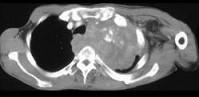

问题 男,68岁,咳嗽,胸痛,呼吸困难伴四肢无力半月余,请结合影像学检查,选出最可能的诊断 ( )

选项 A.肺癌 B.肺结核 C.淋巴瘤 D.纵隔畸胎瘤 E.恶性胸腺瘤

答案 E